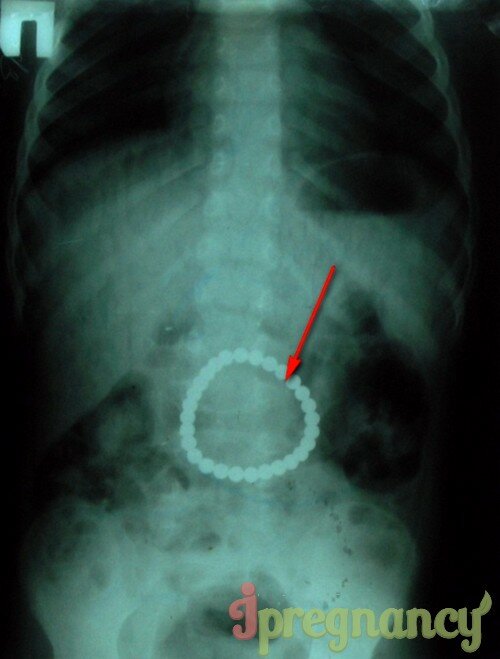

Магнитные шарики на рентгене: Интересные находки

Раздел: Картинки на заметку